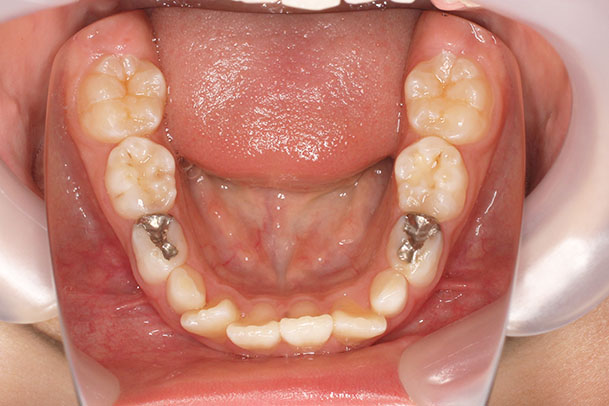

歯が重なっている、出っ歯を治したい 以前に治療した方からの紹介で来院した患者さんです。 上下顎前歯部の叢生(がたつき)、上下顎前歯の前方傾斜、 骨格的上顎前突傾向でした。 小児矯正で叢生の緩和を行い、 本格矯正で前方傾斜した前歯の改善を行いました。 マルチブラケット 動的治療期間 3年3か月 調整回数25回

平均来院間隔1.5か月に1度の来院でした。 治療後は後戻りの軽減するために、親知らず(第三大臼歯)の抜歯をお勧めしています。